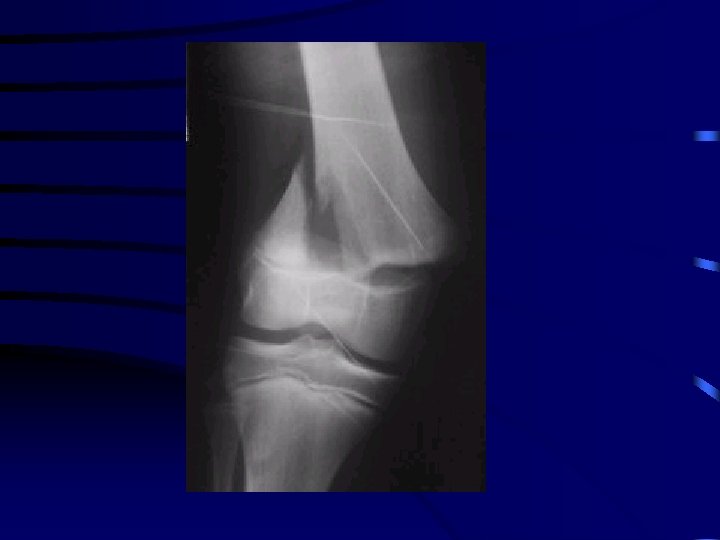

Particularité : le coude • L'examen clinique doit recher : · une atteinte nerveuse : médian (et en particulier l'atteinte du nerf inter-osseux antérieur), radial ou ulnaire · une atteinte vasculaire : recherche du pouls radial • Bilan radio : radiographie du coude Face et Profil

Recherche épanchement